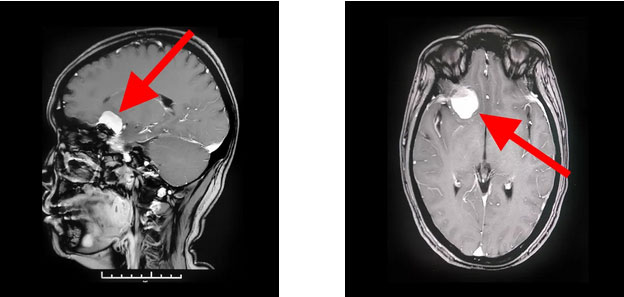

▲ 蝶骨嵴脑膜瘤周围多重要神经血管

▲ 术后影像显示,肿瘤已被切除